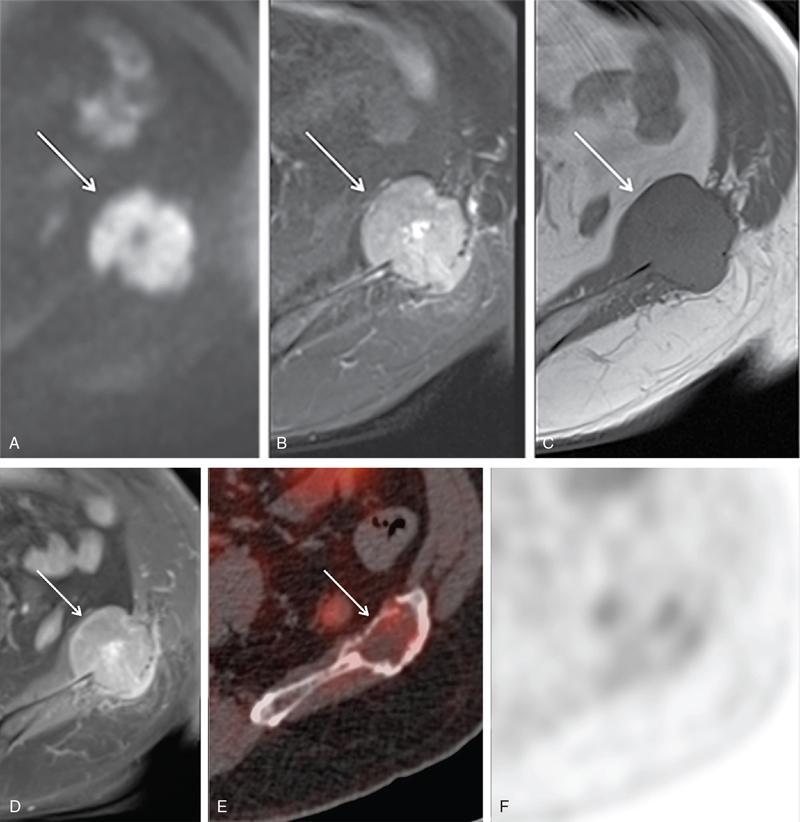

Karthik Ganesan, Disha Lokhandwala, Ujjwal Bhure, Jay Mehta Morphogenesis of the male genitourinary system is governed by the coherent interaction of three units, namely the Wolffian duct, urogenital sinus and foetal gonads. The Wolffian ducts are the embryonic precursors of the male internal genitalia, arising in the anterior intermediate mesoderm at 4 weeks of gestation. They elongate as a cord of cells that caudally extend to the urogenital sinus. Between 5 and 8 weeks of gestation, the urorectal septum divides the cloaca into a ventral compartment, which forms the urogenital sinus, and a dorsal compartment, which forms the rectum. The gonads form as epithelial thickenings on the ventromedial surface of the mesonephros and produce testosterone at 8 weeks of gestation, reaching a peak at 10–15 weeks. Under the effect of testosterone produced by the foetal testis, the prostate anlage forms at the tenth week of gestation. Precursor of the anlage begins with proliferation of solid epithelial buds from the epithelium of the urogenital septum into the adjoining mesenchyme in response to interaction of 5α-dihydrotestosterone with mesenchymal androgen receptors. As growth progresses, solid cords of epithelial cells are formed, growing into the mesenchyme in a specific three-dimensional arrangement (establishes the lobar divisions of the prostate gland). These solid cords develop a central lumen at birth and are lined by a layer of flat basal epithelium and a luminal layer of tall columnar secretory epithelium. Mesenchymal component forms the stroma, which has a large proportion of smooth muscle. Postnatally, the epithelial cords continue to arborize till puberty without any change in volume or glandular architecture. Although the foetal prostate has been described to have a histologically distinct peripheral zone (PZ) as early as 12 weeks of gestation, the mature zonal anatomy develops in concordance with the androgen surge at puberty. The most commonly utilized ultrasonographic technique for the evaluation of the prostate is via a suprapubic approach. The abdominal transducers used in this approach are relatively low frequency and while it offers the advantage of greater depth of penetration without intracavitary probe insertion; however, it does not depict the zonal anatomy and its chief application lies in volume estimation. Hence, transrectal ultrasonography (TRUS) completely outweighs the transabdominal approach in terms of depicting zonal anatomy, visualizing and localizing small lesions, demonstrating vascularity and performing biopsies. TRUS is performed using high frequency transducers (5–7.5 MHz) to optimize soft tissue resolution. An enema is administered 1 h prior to the examination to clear the field of insonation. Patient is positioned in left lateral decubitus, with knees bent toward the chest and ideally a digital rectal examination (DRE) is conducted prior to probe insertion. The transducer is first draped with a sterile barrier and lubricated, After insertion, the barrier is filled with 40–50 cc of water, making sure that no air enters. On completion, water is aspirated and the probe is withdrawn. The gland is initially scanned in the axial plane from the base to the apex, beginning at the level of the seminal vesicles, and the probe is gradually withdrawn to view the entire glandular parenchyma in axial sections up to its caudal aspect. This approach allows a cursory evaluation of glandular symmetry as both halves of the prostate can be evaluated simultaneously. Subsequently, sagittal views are acquired by rotating the probe across the transverse span of the gland, demonstrating the seminal vesicles, midline gland (visualizing both the apex and the base), with sequential scanning up to the contralateral margin of the gland. Sonographically, the prostatic capsule is seen as a smooth well-delineated, hyperechoic structure. With the newer ultrasound systems, the zonal anatomy can be delineated by TRUS; PZ appears echogenic relative to the central zone (CZ) and the transition zone (TZ), which are hypoechoic in juxtaposition (Fig. 11.12.1). Anterolaterally, the preprostatic venous plexuses are seen as anechoic tubular structures with intervening echogenic preprostatic fatty tissue. Glandular volume is estimated using an ellipsoid formula by obtaining the maximum anteroposterior, superoinferior and transverse dimensions and multiplying their product by π/6. Colour Doppler imaging is utilized to illustrate vascularity, as majority of the normal prostatic tissue (excluding the neurovascular bundles [NVBs] and pericapsular and periurethral regions) has symmetrical but sparse flow and an increased microvessel density raises the suspicion of prostatic carcinoma. However, the appearances of prostatic carcinoma can be variable on colour Doppler imaging, ranging from focal increase in vascularity around a nodule to an asymmetric increase in size and number of vessels on the affected side and conventional Doppler has found to elevate specificity by about 5%–10%. Additionally, Doppler imaging has also demonstrated some utility in distinguishing fibrotic tissue from local recurrence. However, vessels supplying cancerous tissue are of the order of 10–50 μm, which is well below the 1-mm resolution limit of conventional Doppler techniques. Contrast-enhanced colour Doppler imaging overcomes this limitation and facilitates imaging of microvessels, using intravenously administered microbubbles (less than 10 μm diameter) of an inert gas (sulphur hexafluoride) with a lipid or galactose shell, allowing quantification of blood flow in the cancerous microvessels. Additionally, these microbubbles act as vascular tracers and by monitoring the passage of a bolus injection through the tissue of interest, time–intensity curves are created. This permits the formulation of functional indices, including bolus arrival time, time to peak intensity, area under the curve and wash-in/wash-out curves. These indices can further extrapolate functional images, on a pixel-by-pixel basis, overlaid on grey-scale images. Quantitative methods to demonstrate perfusion are based on the destruction of microbubbles by high-power ultrasound pulses, and then observing the rate of microbubble replenishment in the field of interest to calculate flow rate. Halpern et al. utilized contrast-enhanced ultrasound and intermittent harmonic imaging with power Doppler, and exhibited an increment in sensitivity from 38% to 65% with a specificity of 80% in prostate cancer detection. Cadence contrast pulse sequencing (CPS) is a low-power multipulse imaging technique utilizing pulses with variable amplitudes and phases followed by a summation of the resulting echoes, permitting tissue suppression, allowing detection of even a small amount of contrast agents retained in the tissues. Real time elastosonography evaluates and quantifies tissue stiffness (Young’s modulus) by measuring strain under an applied stress (transducer compression) and maps areas of variable stiffness in colour-coded and grey-scale images simultaneously and shows potential in improving prostatic carcinoma detection. In a study comparing elastography and T2-weighted (T2-w) endorectal magnetic resonance imaging (MRI), similar sensitivity rates and negative predictive values (NPVs) were attained in the detection of prostatic carcinoma. Prostate gland is an inverted cone-shaped subperitoneal retropubic gland, with its base located rostrally and apex located caudally. The base is attached to the bladder neck and the apex sits on the urogenital diaphragm and abuts the medial surface of the levator ani muscles, namely the pubourethralis portion, which is separated from the inferolateral surfaces of the gland on either side by the prostatic venous plexus. Normal prostate gland measures approximately 4 × 3 × 3 cm, 15–20 g in weight, with a median volume of 11.5 mL (range, 1.6–20.6) in patients between 21 and 25 years and a median volume of 39.6 mL (range, 13–169.8) in patients between 38 and 83 years. The first comprehensive publication describing the anatomical subdivision of the prostate gland was in 1912 by Lowsley, based entirely on the embryonic glandular morphology at a series of gestational age groups. The budding prostatic ducts were seen to proliferate in five distinct clusters from the primitive urogenital sinus, which formed the basis of its lobar subdivision. It was divided into a ventral lobe (anterior to the urethra), two lateral lobes (lateral to the ejaculatory ducts), a posterior lobe (between the ejaculatory ducts) and a middle lobe (above the ejaculatory ducts). This classification had several shortcomings, the foremost being inclusion of only the embryonic prostate during its conception. Frank highlighted these aspects in 1953 and stated that no definite lobar boundaries exist in the adult prostate and further criticized the exclusion of periurethral glands (inner gland), identifying them as the sole site of origin of benign prostatic hyperplasia (BPH). The chief drawback of all research prior to 1968 was the lack of a concrete histological basis to support the seemingly arbitrary subdivision. McNeal was the first to ascertain histological heterogeneity within the glandular tissue and used it as the basis of his well-acclaimed prostatic zonal classification. The zonal anatomy of the prostate gland conceived by McNeal divided the gland into four distinct zones, namely the TZ, PZ, anterior fibromuscular zone (AFMZ) and the CZ (Fig. 11.12.2). McNeal used the plane of the distal urethra to describe the zonal relationships and divide the gland broadly into three parts, namely the base, midgland and the apex (Fig. 11.12.3). The improved understanding of the prostate anatomy coincided with the development of MRI in the late 1980s, which could depict the zonal anatomy, unlike ultrasonography (USG) or computed tomography (CT). Patterns of ductal growth and radiation from the prostatic urethra form the basis of the zonal anatomy of the gland. Ducts arising from the proximal urethral segment grow towards the urinary bladder. Tiny ducts which are confined by the preprostatic sphincter form the small periurethral gland, whereas ducts which develop distal to the lower border of the preprostatic sphincter extend laterally and then anteromedially to form the TZ. Ducts arising from the verumontanum in the vicinity of the ejaculatory duct orifices and are directed towards the base along the course of the ejaculatory ducts form the CZ, whereas ducts which arise from the lateral recess of the posterior urethral wall of the verumontanum and distal urethra radiate laterally to form the PZ and rostrally posterior to the CZ at the base of the gland. PZ is the dominant glandular component of the prostate gland comprising approximately 70% of the glandular tissue. On T2-w images, the normal PZ has a high T2 signal intensity (SI), owing to the abundant ductal and acinar elements with sparsely interwoven smooth muscle, and can broadly divided into three sections as per the sector map in Prostate Imaging Reporting and Data System Version 2.1 (PI-RADS v2.1), namely posterior medial, posterior lateral and anterior sections (Fig. 11.12.4). At the apex, the anterior sections have a horn-like morphology, curving anteromedially, to nearly encircle the urethra and abut the AFMZ. At the midgland level, the PZ comprises the posterior, both lateral and the anterolateral parts of the gland. At the base, the PZ is located posterior and superior to the CZ and TZ. CZ is an ovoid-shaped structure at the base of the gland, comprising approximately 25% of the glandular tissue, with its apex located at the verumontanum, surrounding the ejaculatory ducts. Beyond age 35, volume of the CZ starts to gradually diminish, as well as the CZ is compressed by the enlarged TZ. In the initial MR studies of prostate, the CZ could not be easily delineated from the TZ. Vargas et al. demonstrated in a population with a mean age of 60 years undergoing MR for prostate cancer assessment, the CZ was visible in 81%–84% of patients. Hansford et al. identified the CZ in 92%–93% of patients on T2-w images and 78%–88% of patients on apparent diffusion coefficient (ADC) maps. Histologically, substantial differences exist between the CZ and PZ, which reflect in the differential appearance on T2-w imaging. These differences are probably attributable to the differential origin, as the CZ is derived from the Wolffian duct, and the PZ and TZ are derived from the urogenital sinus. In the CZ, the acini appear larger and more irregular, with numerous epithelial covered ridges or septa project from the walls of the acini into the lumen, forming a characteristic Roman bridge architecture and intraglandular lacuna, with a prominent basal layer, crowded epithelial cells with granular eosinophilic cytoplasm, decreased luminal fluid and compact stroma. PI-RADS v2 has discouraged the use of the term central gland, as it is not reflective of zonal anatomy or reported on pathologic specimens. CZ demonstrates homogeneously low signal on the T2-w images and ADC maps and can, therefore, mimic prostate cancers. CZ is best identified on the coronal plane T2-w images paralleling the plane of the distal urethra, and appears as a symmetric paramedic paired structures surrounding the ejaculatory ducts from the base of the gland to the verumontanum (Fig. 11.12.5). TZ comprises approximately 5% of the glandular tissue of the prostate. On T2-w images, the TZ normally appears as a homogeneously hypointense structure surrounding the proximal urethra at the base and the midgland level; however, it can also demonstrate inconsistent SI, depending on the relative proportion of glandular and stromal elements (Fig. 11.12.6). Glandular hyperplasia produces higher SI (dominance of acinar elements and secretions), while stromal hyperplasia exhibits lower SI (dominance of muscular and fibrous elements). The TZ is easily demarcated from the PZ by a thick homogeneously low T2 signal surgical capsule, which becomes pronounced in BPH. With increasing age, the TZ demonstrates variegated signal on the T2-w images and ADC maps, due to differential growth of the stromal and glandular elements. AFMZ is a nonglandular muscular tissue that drapes the anterior surface of the gland, superiorly blending into the smooth muscles of the bladder neck and inferiorly extending to the prostatic urethra at the glandular apex. AFMZ is comprised of smooth muscles, which blends with the smooth muscle fibres surrounding the urethra, and rostrally merges with the bladder neck and preprostatic sphincter. High smooth muscle content of the AFMZ is responsible for the MR signature, where in it appears markedly hypointense on the T2-w images and ADC maps, and hypoenhances on the multiphase contrast series (Fig. 11.12.7). With the advancing age, temporal reduction in the size of the AFMZ is noted due to the compressive effects of the BPH. Capsule surrounds the prostate gland, anteriorly merging with the AFMZ anteriorly. Two discrete defects are identified in the prostate capsule, at the base of gland where the ejaculatory ducts enter the prostate and at the apex where in the stroma blends with the sphincter. The capsule is perforated along the anterolateral aspect by multiple vessels and nerves. The capsule appears as a thin dark rim surrounding the gland on the T2-w images and may reveal delayed enhancement on the postcontrast images (Fig. 11.12.8). Primary goal of radical prostatectomy (RP) is to achieve oncologic efficacy, both in terms of short-term and long-term clinical outcomes. However, as the majority of prostate cancers have an indolent clinical course, preservation of function in terms of continence and potency is equally important, and the key to this is a keen understanding of the fascial anatomy and neuroanatomy of the prostate gland. Fascial anatomy of the prostate gland is anatomically complex and poorly understood, and a thorough understanding of the interfacial planes is crucial to avoid mechanical or thermal injury to the NVBs. Periprostatic fascia comprises of a condensation of layers of connective tissue that encapsulate the gland and suspend it from anterior pelvic wall via puboprostatic ligaments. Laterally, the visceral and parietal endopelvic fascial layers fuse to form the fascial tendinous arch. Periprostatic fascia covers the prostate gland and capsule, comprises of two fascial layers, including an inner layer (prostatic fascia) and an outer layer (levator ani fascia), with thin interfascial planes separating these fascia from one another and the prostate capsule. Posteriorly, a continuous fascial layer known as Denonvilliers’ fascia covers the prostate and seminal vesicles. Distribution of periprostatic nerves is highly variable, with growing evidence of nerves both along the dorsolateral and ventrolateral surfaces of the prostate gland. Most of the periprostatic nerves are found posterolaterally; however, a significant portion of the nerves are located ventrally as seen by Eichelberg et al. (21.5%–28.5%) and Lee et al. (19.9%–22.8%). Although anatomic studies have confirmed the presence of ventrolateral periprostatic nerves, the exact clinical importance and functionality of these nerve fibres has not been proven. The cavernous nerves are situated posterolaterally and are the basis of nerve-sparing RP procedure proposed by Walsh and Donker. Unlike the initial theory of Walsh and Donker, few papers have proposed that the nerves are diffusely scattered along the surface of the gland in the form of a curtain or spray-like arrangement without clear bundle formation. Kourambas et al. assessed the precise relationship of the NVBs and cavernous nerves to Denonvilliers’ fascia and proposed that the nerves were not restricted posterolaterally, but were rather diffusely scattered within the fascia extending up to the midline (Lunacek et al., Takenaka et al.). On the basis of more diffuse arrangement of the periprostatic nerves, surgical techniques have been modified, resulting in a more anterior dissection called the ‘curtain dissection technique’ or alternatively a ‘superveil’ technique to preserve the NVBs within the lateral prostatic fascia. The NVB lies within areolar connective tissue surrounding the gland, which separates the capsule from the periprostatic fascia and provides a plane of dissection during nerve-sparing prostatectomy. Prostate gland is supplied and drained by periprostatic vessels, which also supply and drain the penis. Arterial supply of the gland is highly variable and is typically from branches of the internal pudendal artery, which course inferior to the gland prior to supplying the penile cavernosal tissue. Off late, these vessels have gained prominence in radiation-induced erectile dysfunction (ED) (potential vasculopathy), which have led to the development of newer vessel-sparing radiotherapy techniques. Further, with the advent of prostate arterial embolization in benign prostatic hypertrophy (BPH), the vascular supply of the gland is becoming increasingly vital to understand. Gland drains into the obturator, internal iliac, external iliac, common iliac and presacral lymph nodes. Dorsal venous complex is identified immediately ventral to the gland and also drains the penis. Periprostatic nodes are uncommon, are usually discovered near the base of the gland, and are only occasionally seen on MRI. Urethra is the principal anatomic reference point in the prostate gland. Urethra can be divided into a proximal segment and a distal segment, the point of differentiation being located at the verumontanum wherein the urethra makes an approximately 35-degree angulation. The angulation is highly variable and is further affected by the growth of the TZ. On MRI, the distal segment is more conspicuous vis-à-vis the proximal segment and appears a hyperintense core surrounded by a low signal rim on T2-w images. Preprostatic sphincter encases the proximal urethra from the base of the gland to the base of the verumontanum and merges with the AFMZ anteriorly. Verumontanum appears hyperintense on the T2-w images, lies within the distal urethral segment, beyond which the distal urethral segment is partially encircled by striated muscles which blend with the external sphincter beyond the apex of the gland. External sphincter is located distal to the apex is incomplete posteriorly and is anchored into the PZ and surrounds the membranous urethra. Damage to the external sphincter during RP or transurethral resection of the prostate (TURP) may lead to urinary incontinence. Seminal vesicles are paired structures identified posterosuperior to the base of the prostate gland, which appear as convoluted fluid-filled structures. Due to the high fluid content within the normal seminal vesicles, these structures appear as paired structures with intermediate signal walls surrounding a hyperintense core on T2-w images (Fig. 11.12.9). Vas deferens are paired structures located rostral to the base of the gland and anteromedial to the seminal vesicles and appear as cord-like structures with variable signal on the T2-w images. Duct of the seminal vesicle and vas deferens unite in the posterior aspect of the base of the gland to form the ejaculatory duct, which courses caudally to the verumontanum along the plane of the distal urethra, and drain into the orifices in the midconvexity of the verumontanum. Prostate-specific antigen (PSA) is a serine protease, secreted by epithelial cells of the prostate gland and has been found in normal, benign and malignant prostatic tissues. Traces of PSA have also been isolated from endometrial tissue, breast tissue, adrenal neoplasms and renal cell carcinomas; however, for all clinical purposes, PSA is considered as an organ-specific biomarker. Papsidero first demonstrated and quantified serum PSA, which steered the epoch of prostate cancer screening and early detection of prostatic carcinoma. Subsequent studies showed that PSA screening often led to overdiagnosis of low-grade prostate cancers, with no survival difference between the PSA screened and nonscreened groups. Additionally, PSA levels were found to be elevated in a spectrum of prostatic pathologies apart from carcinoma, including prostatitis and benign hyperplasia. The likelihood of overdiagnosis coupled with the lack of specificity set grounds for the longstanding PSA controversy. Did the benefits of screening outweigh the risks of overtreatment? To elevate the specificity of serum PSA testing, a plethora of indices were devised, including free PSA and total PSA, free-to-total PSA (f/t PSA) ratio, age-specific PSA, PSA velocity (PSA-V) and PSA density (PSAD). Serum PSA exists in three forms; the major form (approximately 75%) is bound to alpha-1-antichymotrypsin, followed by free PSA (constituting 5%–50% of serum PSA). The third form (PSA bound to alpha-2-macroglobulin) is not clinically relevant and cannot be detected by any commercial test. A study by Stenman et al. established that a higher proportion of bound PSA and hence a lower ratio of f/t PSA is associated with prostate cancer. Conversely, free PSA can be utilized during follow-up for men with an initial negative biopsy result, wherein declining free PSA with a persistently elevated total PSA would raise suspicion of a neoplastic aetiology. As per the ACS guidelines (Table 11.12.1) for early detection of prostate cancer, men with a 10-year life expectancy or higher should have the opportunity to make an informed (regarding benefits, risks and uncertainties associated with PSA screening) decision for serum PSA testing, with or without DRE. For those who choose to undergo PSA screening, subsequent screening interval is determined on the basis of baseline PSA value. For values below 2.5 ng/mL, screening interval can be extended to 2 years and for PSA between 2.5 ng/mL and 4 ng/mL, an individualized approach is adopted following risk assessment to recommend either further referral or screening on a yearly basis. A PSA level of 4 ng/mL or higher warrants referral for further evaluation or biopsy, for men at average risk for prostate cancer. Although age-specific PSA (Table 11.12.2) is not a component of the ACS guidelines, it is considered as a beneficial parameter in determining the need for biopsy. As there is an expected rise in PSA values with age, setting a lower cut-off value for younger men would increase the sensitivity of detecting organ confined cancers and a higher value in older men would increase specificity. aThere is no proven rationale for using a single PSA-V threshold value. PSA screening guidelines for treated localized prostate cancers are variable and the definition of biochemical (PSA) recurrence remains debatable. Due to this inconsistency, the Prostate Cancer Guidelines Update Panel recommended a standard definition for biochemical recurrence (BCR) after RP and set a cut-off serum PSA (acquired between 6 weeks and 3 months of surgery) of 0.2 ng/mL or greater, along with a second confirmatory PSA. While there is a significant fall in PSA values after RP and a single raised PSA is sufficient to raise suspicion of recurrence, postradiotherapy recurrence requires a rising trend rather than a single cut-off value. The ASTRO Consensus Panel defined postradiotherapy prostate cancer recurrence as three consecutive raises in PSA values after a baseline has been reached. A hiatus in this definition was that no specific time interval between consecutive increases in PSA was determined. In addition to its utility as a screening tool, PSA is also a good prognosticator when used in conjunction with biopsy Gleason score and clinical T-stage, and several pretreatment prostate cancer risk stratification systems are based on these indices. D’Amico et al. proposed a three-group risk stratification system in 1998, which categorized nonmetastatic (M0) carcinomas as low risk, intermediate risk and high risk. Low-risk prostate cancer was defined as 1992 AJCC T1/T2a, PSA ≤10 ng/mL and Gleason score ≤6. Intermediate-risk prostate cancer was defined as 1992 AJCC T2b, and/or PSA 10–20 ng/mL and/or Gleason 7 disease. High-risk disease included any one of the following: 1992 AJCC ≥T2c, PSA >20 ng/mL or Gleason 8–10 disease. In 2001, the GUROC published the results of a consensus meeting which categorized the groups as follows: low risk – 1997 AJCC T1–T2a, PSA ≤10 ng/mL and Gleason ≤6; intermediate risk – 1997 AJCC T1–T2, PSA ≤20 ng/mL and Gleason ≤7 not otherwise low risk and high risk – 1997 AJCC T3–T4 or PSA >20 ng/mL or Gleason 8–10. In due course, newer classification systems have been developed (Table 11.12.3), including the National Comprehensive Cancer Network (NCCN, USA), National Institute for Health and Clinical Excellence (NICE, UK), European Society of Medical Oncology (ESMO), American Urological Association (AUA) and the European Association of Urology (EAU). The NCCN guidelines also incorporate very low-risk (T1c, and Gleason score ≤6, PSA ≤10 ng/mL, <3 positive biopsy cores each ≤50% involved and PSAD of <0.15 ng/mL/g) and very high-risk (T3b–T4) categories. AUA, American Urological Association; EAU, European Association of Urology; GUROC, Genitourinary Radiation Oncologists of Canada; NICE, National Institute for Health and Clinical Excellence; CAPSURE, Cancer of the Prostate Strategic Urologic Research Endeavour; NCCN, National Comprehensive Cancer Network; ESMO, European Association of Urology; T, T-stage; GS, Gleason score; PSA, prostate-specific antigen. Note: Use of the 1997 TNM staging system (T2a one lobe involvement, T2b two lobes involvement, no T2c category). PSA, DRE and TRUS form the diagnostic triad for prostatic carcinoma. It has been well established that manipulations of the prostate gland, including prostatic massage, cystoscopy and perineal biopsy cause a potential increase in serum PSA levels. This raised the question of TRUS affecting PSA levels and it was found to cause a very small rise in PSA only in patients with prostatitis. The effect of DRE on serum PSA levels is also controversial, while some studies found a transient increase in PSA, others found no significant rise in PSA levels after DRE. Therefore, it is advisable to obtain blood samples for PSA testing either prior to DRE and TRUS or after at least 7 days. PSA-V refers to the change in PSA over time using serial measurements. Ideally, at least three consecutive measurements over at least 18–24 months should be used. Carter et al. first defined PSA-V and found that a value of 0.75 ng/mL per year or greater was indicative of carcinoma with a high sensitivity and specificity. Consequently, several studies disproved a definite relationship between PSA-V and prostate cancer, stating that there was no rationale behind a single threshold value for PSA-V. Further, it was found that calculating PSA-V was arduous and while elevated PSA values on serial examinations should raise alarm, there was no added benefit of formally calculating PSA-V. As per NCCN guidelines, the PSA-V cut-off should be based on the initial PSA value with a PSA-V of 0.35 ng/mL/y, when the PSA is ≤2.5 ng/mL and 0.75 ng/mL/y, when the PSA is 4–10 ng/mL PSAD was developed in order to correlate prostate volume and PSA values. The basis of PSAD was that cancer cells produce more PSA per unit volume than normal cells. It is calculated as PSA value divided by the prostate volume as determined by TRUS. This reliance on TRUS leads to interobserver variability and hence PSAD values would differ with the performing sonologist. The chief utility of PSAD is in the diagnostic grey zone of PSA values between 4 and 10 ng/mL and the most commonly used cut-off value is 0.15 ng/mL/cc. However, more recent studies have shown that a value of 0.08 ng/mL/cc has an NPV of 95% in predicting prostate cancer. Additionally, PSAD in conjunction with MRI (PI-RADS score) has proved to be a reliable prognosticator for Gleason score upgrading. The most significant application being avoiding unnecessary biopsies as PI-RADS scores of 1–3 along with PSAD values <0.15 ng/mL/cc showed no Gleason score upgrading on repeat biopsies. In summary, most guidelines recommend shared decision-making for screening of prostate cancer. Limited testing should be conducted in men with low PSA values and a lower life expectancy. The aim should be to overcome challenges posed by the inherent nonspecific nature of serum PSA and reduce superfluous testing, unwarranted biopsies and overdiagnosis. Reliance on parameters like PSA-V that do not have a proven scientific basis is avoidable. Whereas applications of PSA like PSAD along with MRI can greatly reduce patient burden by avoiding follow-up biopsies. Lastly, PSA has no role in assignment of a PI-RADS category, which is based on multiparametric MRI (mpMRI) findings alone. Several ‘novel biomarkers’ are now being developed which are more specific in detecting high-grade prostatic carcinomas. Other human kallikrein proteins have been identified, as prostate cancer biomarkers, of which, human kallikrein 2 (hK2) has shown a high specificity. While hK2 and PSA have an overlapping primary structure, malignant cells express hK2 to a higher degree than benign epithelial cells, particularly in aggressive cancers. Engrailed-2 (EN2) is an HOX gene family transcription factor seen exclusively in malignant prostate tissue, with a reported sensitivity and specificity of 66% and 88%, respectively. Annexin A3 is a calcium-binding protein measured in urine samples following prostatic massage, potentially reducing unnecessary biopsy in men with a PSA of 2–10 ng/mL. However, extensive prospective evaluation of these biomarkers is necessary to replace PSA testing in clinical practice. Positron emission tomography (PET)/CT has evolved over the last two decades to make a paradigm shift in the field of imaging, moving from morphological imaging to molecular level and completely changing the approach to how we view the disease. Though the main workhorse tracer in the field of PET/CT is 18-fluorine-fluorodeoxyglucose (18F-FDG), it has limitations with regard to prostate cancer, especially in indolent or well-differentiated ones. However, that void has been filled up by the new kid on the block and that is prostate-specific membrane antigen (PSMA)-based radiotracer. PSMA is a type II transmembrane protein with intracellular (19 amino acids), transmembrane (24 amino acids) and extracellular (707 amino acids) domains, which functions biochemically as a glutamate carboxypeptidase. After a ligand binds to PSMA, internalization occurs and it is either retained in lysosomal compartments or released into the cytoplasm. PSMA expression and localization in the normal human prostate is associated with cytoplasm and apical side of the epithelium surrounding prostatic ducts but not basal epithelium and neuroendocrine or stromal cells. Neoplastic transformation of prostate tissue results in the transfer of PSMA from the apical membrane to the luminal surface of the ducts. PSMA is an ideal target for molecular imaging of prostate cancer as its expression is significantly upregulated in prostatic carcinoma cells compared to benign prostatic tissue, in density (100 to 1000 times) as well as activity (8 to 10 times). PSMA expression increases with increase in Gleason score, stage and grade of tumour, with further increased expression with transition to androgen-independent/castration-resistant prostate cancer. PSMA-binding analogues, because of their high sensitivity and specificity, possess precise imaging characteristics required for critical decisions in the management of prostate cancer (PCa). The most commonly used PSMA radiotracer is 68Gallium-PSMA-11, followed by 18F-PSMA. The availability of 18F-labelled PSMA radiopharmaceutical has helped to advance the reach of PSMA PET imaging to wider locations owing to higher available amount of the radiotracer due to its production from a cyclotron, compared to 68Ga-PSMA which is eluted from individual in-house generator. Additional benefit is accrued with excellent image quality owing to optimized radiotracer doses, higher imaging statistics and favourable decay properties of 18F radioisotope. The normal physiological biodistribution of PSMA-based radiotracers is seen in lacrimal and salivary glands, liver, spleen, kidneys and intestine. Physiological activity is also seen in celiac and cervicothoracic ganglia. Unbound PSMA radiotracer is excreted by the kidneys into the urinary bladder. PSMA PET/CT has established roles of varying degrees in the imaging of different aspects of prostate cancer including primary diagnosis, staging, BCR after primary prostate cancer treatment (prostatectomy), identification and significance of oligometastasis, restaging and treatment response assessment and monitoring. PSMA PET/CT is useful at the stage of diagnosis in that subset of patients with tumour-negative biopsy samples, by contributing the useful molecular information to mpMRI, helping to precisely delineate suspicious lesions for targeted biopsies. In intermediate-risk to high-risk primary prostate cancer patients, PSMA-based imaging has shown improvement in detection of metastatic disease compared to the CT and mpMRI, which has led to reduced demand and dependence on additional cross-sectional imaging or bone scintigraphy. Furthermore, PSMA PET/CT has also established its clear advantage over conventional imaging in patients with biochemically recurrent prostate cancer with improved and increased detection of metastatic sites even at low serum PSA values. As it happens in cancer, biopsy is the standard of diagnosis and likewise in PCa, it is the multicore biopsy, which is the gold standard. However, because of its size, location, approach and sensitive and delicate nature, yield and accuracy can often be restricted, especially in inexperienced hands. The diagnostic yield of biopsy can go down as low as 40% and false negative (FN) rate can climb as high as 25%–30%. PSMA overexpression follows high-grade PCa cells and increases with Gleason score. In normal prostate tissue, PSMA to PSA ratio is about 1, which decreases in BPH, increases in primary PCa cells, further increases with intratumoural angiogenesis, higher in metastatic lesions than in primary PCa cells and further upregulated in castration-resistant situation. In a study by Litwin and Tan in 2017, the FN rate of multicore biopsy was around 21%–28% and about 15% of the cases were undergraded vis-à-vis final prostatectomy results. While the diagnostic accuracy of random multicore biopsy was around 76.3%, that of 68Ga-PSMA PET/CT was upward in the range of 85.5%. The role of PSMA PET/CT in the primary/initial diagnosis of prostate cancer is generally limited to clinically intermediate-risk to high-risk patients with negative biopsy or reluctance to biopsy or noncooperation or nonfeasibility and for confirmation and staging in clinically high-risk patients. In low-risk patients, metastatic spread is very unlikely and hence it is a relative indication at the time of initial diagnosis in low-risk patients. And, its role in screening is variable and debatable (Fig. 11.12.10). Staging is crucial as it has considerable influence on deciding further line of management and treatment choices, which includes RP, radiotherapy or palliative systemic treatment, deciding on the extent of the pelvic nodal dissection during surgery, planning the radiotherapy field and consideration of multimodal therapy. Accurate staging helps to make the most appropriate choice of treatment modality (Fig. 11.12.11). In a meta-analysis of five studies with histopathology as gold standard, which included 216 patients, the per-lesion sensitivity of 68Ga-PSMA PET/CT ranged from 33% to 92% (33% value being an outlier due to the retrospective analysis based only on the reports, in absence of the images) with higher specificity of 82%–100%. For T-staging, PSMA PET/CT showed a significantly higher tumour detection rate of 92% vis-à-vis 66% with MR alone. In regard with N-staging, the majority of metastatic nodes from prostate cancer are small subcentimetre-sized, less than 8 mm, which are overlooked, missed or inconclusive on morphological imaging (CT and MRI) (falling below size criteria for morphological imaging). Accurate N-staging is important because lymph node involvement is a critical prognostic factor in cancer management, and precise pelvic nodal clearance could be curative and could make a difference in treatment success and long-term outcome in prostate cancer (Fig. 11.12.12). Also, accurate prediction of pelvic nodal metastases may spare nodal dissection, shorten surgical time and in turn help to reduce undesirable complications. In one study from 2016 involving 130 patients with intermediate-risk to high-risk prostate cancer, the metastatic nodal detection rate by 68Ga-PSMA PET was around 66% compared to 44% with MRI. PSMA PET has shown superior predictive value for surgical response over Gleason score, pT stage and PSA (at the time of imaging). In a literature overview by Luiting et al. in 2019 involving 9 retrospective and 2 prospective studies, the specificity of PSMA PET/CT in detection of pelvic nodal metastases before initial treatment reached as high as 80%–100%. PSMA PET/CT increases the confidence level in the evaluation of nodal metastases and an NPV reaching up to 86%. With imaging becoming more precise and adding different modalities together, the question arises about the tiny nodes less than 5 mm size. In a study by van Leeuwen et al. in 2017, the mean size of missed lymph node metastases was 2.7 mm. In a recent study by Ferraro et al. in 2020, about the impact of PSMA PET staging on clinical decision-making in intermediate-risk to high-risk prostate cancer patients, PSMA PET provided new information in 36% of patients and this helped to change treatment decision in nearly 27% of patients, which means in every fourth patient they studied. PSMA PET in combination with CT or MRI can achieve complete and precise Tumor, Nodes and Metastases (TNM) staging including staging of local tumour, nodal assessment and bone and organ/visceral metastases, in one single imaging session, with improved accuracy and better outcome, and in turn leading to precise treatment planning, eventually superseding conventional imaging. Accurate localization of prostate cancer lesions in patients with BCR is a major challenge. Especially at low serum PSA values (as low as less than 0.5 ng/mL), the precise determination of localized disease and metastatic spread is of great importance for further disease management. Conventional imaging modalities including CT scan or bone scintigraphy have limited detection rate for metastatic disease at low serum PSA values in this setting of BCR. PSMA PET/CT imaging plays a very valuable role in the evaluation of BCR (Fig. 11.12.13), which is indeed very critical and important aspect in prostate cancer management. The international consensus on BCR includes PSA >0.2 ng/mL for two times after prostatectomy, or PSA nadir + 2 ng/mL after radiotherapy or brachytherapy. With the incorporation of PSMA PET/CT in the imaging armamentarium, the overall detection rate for local recurrence as well as metastases with BCR after prostatectomy reached up to 90%. The detection rate increases with rising PSA level, jumping over 90% with PSA level going above 1 ng/mL. In a homogeneous consecutive cohort of 248 patients with BCR after RP with mean serum PSA value of 1.99 ng/mL, studied by Eiber et al., 68Ga-PSMA PET/CT showed detection rates of 57.9%, 72.7%, 93.0% and 96.8% for patients with serum PSA values of 0.2–<0.5 ng/mL, 0.5–<1 ng/mL, 1–<2 ng/mL and ≥2 ng/mL, respectively. Tumour Gleason score or androgen deprivation therapy (ADT) did not significantly influence the detection rates (Fig. 11.12.14). These detection rates for 68Ga-PSMA PET are substantially higher than those reported for choline-based PET radiotracers, which fell between 19% and 36% at serum PSA levels of <1.5 ng/mL. The improved detection rates are due to the incremental value of molecular imaging as 68Ga-PSMA PET exclusively showed findings not evident on diagnostic CT in 32.7% of patients with information about additional involvement of different anatomical region in 24.6%. A high PSA-V and short PSA doubling time showed a tendency towards increased detection rates, though not statistically significant. As salvage radiotherapy is most effective at low serum PSA values, optimized radiotherapy planning with precise definition of target volume for concerned lesions for appropriate boost radiotherapy can be achieved with the help of PSMA PET/CT imaging. Lesion detection rate with PSMA PET/CT in the setting of BCR: PSMA PET/CT imaging helps to identify patients with oligometastatic disease who are suitable for salvage therapy with PSMA-radioguided surgery. PSMA radioligands, by the virtue of their high sensitivity and specificity, can be used for intraoperative tracking of even small metastatic prostate cancer lesions that can be well localized and subsequently removed using this radioguided surgery for salvage procedures. Identification and treatment of oligometastatic disease (3 to 5 positive sites) with targeted therapies such as surgery or radiotherapy may allow deferral of systemic therapies such as ADT, thereby delaying and reducing potential morbidity associated with systemic salvage therapy. The fusion of PSMA PET and MRI, instead of CT, may improve detection rates further in patients with very low serum PSA values (<0.5 ng/mL). The addition of mpMRI to PET can improve the diagnostic accuracy because of the higher soft tissue resolution and detection efficacy of mpMRI for local recurrence compared to CT. Advantages of PET/MRI include excellent anatomical and zonal resolution of the prostate gland with T2-w sequences, and additional useful information about suspicious lesions from functional MRI sequences like diffusion-weighted images (DWI) and dynamic contrast-enhanced (DCE) imaging. Early and accurate detection of tumour burden helps to plan further management strategy including salvage pelvic radiotherapy or salvage nodal dissection and eventually improve the prognosis. PSMA PET/CT also plays an important role in mapping the overall tumour burden, and separating oligometastatic disease from multiple metastases (Fig. 11.12.15). PSMA PET/CT also plays an important role in monitoring the treatment efficacy as well. 99mTc-methylene diphosphonate (99m Tc-MDP) (gamma camera-based radiotracer – single-photon emission computerized tomography (SPECT)/CT) or 18F-sodium fluoride (NaF) (PET/CT-based radiotracer) are bone-specific biomarker of osteoblastic activity. 18F-NaF has superior diagnostic performance compared to 99mTc-MDP (phosphonates) bone scintigraphy in detection of bone metastases, because of different radiotracer characteristics (different energy levels) and different scanners (PET/CT scanners vs conventional gamma scanner) leading to better resolution and clarity with 18F-NaF PET/CT scans. NCCN recommends bone scintigraphy in patients with PSA levels of more than 20 ng/mL or patients with T2 disease with PSA levels more than 10 ng/mL. However, their routine use in clinical practice is limited by relative lack of sensitivity and specificity vis-à-vis PSMA PET/CT and also not able to assess soft tissue lesions, which is possible with PSMA PET/CT (Fig. 11.12.16). Bone scans often fail to detect a lesion when PSA is less than 10 ng/mL in the setting of PSA recurrence post-RP, whereas PSMA PET/CT has been sensitive in the detection of lesions even at the PSA level of less than 0.5 ng/mL. Prostate cancer is a leading cause of cancer-related death in men; however, many patients with the prostate cancer do die of other causes. Hence, it is of paramount clinical importance to accurately risk stratify patients, to distinguish those with low risk to intermediate risk who could be managed conservatively or alternatively those with high risk for morbidity and mortality who would benefit from an aggressive line of therapy. Detection, risk stratification, staging, individual centred management, monitoring and surveillance of prostate cancer have undergone substantial evolution with time. MRI of the prostate gland was first described by Hricak et al. in 1983 and for long was used for staging patients with biopsy-proven prostate cancer and also occasionally served as a problem-solving tool. With recent advancements in MR technology, multiparametric imaging has become the cornerstone of the prostate cancer management, aiding in detection, characterization, risk stratification, biopsy guidance, surveillance and monitoring. This has been further enhanced and strengthened with the introduction of PI-RADS v2.0 in 2015 which helped standardize communication between the radiologists and urologists, and aided in the clinical decision-making process. As the role of MRI has expanded from detection to surveillance and monitoring, the entire clinical context needs to be available to the radiologist prior to performing an mpMR in order to optimize reporting. Both the imaging techniques and its interpretation may vary with the clinical context. In patients with no prior history of therapy, both T2-w images and DWI have a greater impact on reporting and interpretation, whereas in patients with prior therapy T1-w DCE imaging plays a more critical role in interpretation. In routine clinical practice, PI-RADS v2 recommends that PSA levels, detailed results of prior prostate biopsies and therapies be available to the radiologist at the time of performing and interpreting MR findings. Postbiopsy intraglandular haemorrhage occurs after image-guided prostate biopsies and is a confounder, which may obscure an underlying cancer. The greater extent of haemorrhage is attributable to the production of citrate within the prostate gland, which acts as an anticoagulant. The rate at which haemorrhage resolves is highly variable, often fully resolving in a shorter period in some patients and alternatively persisting for many months. Haemorrhage exclusion sign is a useful imaging finding, which may allow the radiologist to localize prostate cancer, as cancerous tissue has low levels of citrate and hence the propensity to haemorrhage in cancerous tissue is lower vis-à-vis benign glandular tissue. In addition, postbiopsy haemorrhage produces milder hypointensity on the T2-w and ADC maps vis-à-vis cancerous tissue. Ideally, a timeframe of 6–8 weeks has been suggested between the biopsy and the mpMRI. However, in routine clinical practice, the need to accommodate patients immediately postbiopsy or within a shorter time frame does exist, as the information provided by mpMR does overweigh the impact on haemorrhage on intraglandular tumour detection. Rectal over distension with faecal matter or gas impairs the quality of prostate mpMRI and especially seems to exacerbate artefacts on DWI. These issues seem to impact imaging with phased array coil rather than endorectal examinations. To avoid these artefacts, patients may be instructed to evacuate shortly before the examination, use a laxative or minimal enema prior to the procedure, have a preparatory enema or use antispasmodic agents to reduce potential artefacts from bowel peristalsis. Though various approaches do exist to adequately empty the rectum and minimize the artefacts, there is a lack of consensus on the optimum technique. mpMRI of the prostate gland can be performed on a 1.5 Tesla (1.5 T) or a 3 Tesla (3 T) scanner. Vastly improved signal-to-noise ratio (SNR) is the critical advantage of a 3 T scanner over a 1.5 T scanner, which in terms of prostate imaging translates into acquisition of high quality images with improved spatial and temporal resolutions, and also acquisition of higher quality functional sequences for quantitative imaging. Therefore, increasing field strength results in better detection and characterization of prostate cancer. On the contrary, higher field strength can amplify susceptibility artefacts arising from rectal air or metallic prosthesis. Other than field strength, many factors impact image quality and resolution including scanner model, gradient quality, slew rate, coil architecture and design and the sequence MR acquisition parameters. Prostate examinations are performed using a phased array coil placed over the pelvis. In certain institutions, an additional endorectal coil may also be used to achieve a higher SNR which improve the visualization of the prostate capsule and NVBs. Utilization of endorectal coils has certain drawbacks and results in patient discomfort, increased cost and scan duration and causes gland distortion. Endorectal coils improve imaging quality and local staging; however, with recent advances in coil technologies, phased array surface coils do provide similar high quality resolution images, which allows for accurate local staging. Currently, PI-RADS v2.0 does not insist on the use of endorectal coil and allows radiological practices to select hardware and optimize sequences that are most appropriate for the given clinical setting. mpMRI of the prostate gland is a combination of anatomical (morphological) and functional sequences. As per the PI-RADS v2 guidelines, the key sequences recommended include triplanar high-resolution axial T2-w images, high b-value axial DWI and ADC map and axial T1-weighted (T1-w) DCE images. High-resolution axial T2-w images and DWI are used to initially localize the ‘index lesion’ in the prostate gland. High-resolution sagittal and coronal T2-w images aid in colocalization of the ‘index lesion’ in terms of its spatial relationship with the gland. High-resolution T2-w images are the principal sequences of mpMR and are acquired with a small field-of-view (120–140 mm) in sagittal, oblique axial and oblique coronal planes. The high-resolution oblique axial and oblique coronal T2-w images are acquired orthogonal and parallel to the long axis of the prostatic urethra. These anatomical images provide exquisite demonstration of prostatic zonal anatomy, prostate capsule and periprostatic structures, which allows to accurately detect extraprostatic extension. An alternative to the acquisition of three separate T2-w sequences is the acquisition of a single volumetric 3-D T2-w imaging sequence with small near-isotropic voxels, which can then be retrospectively reconstructed in any plane. However, few concerns regarding the 3-D acquisition exist, including long acquisition time that may predispose to greater motion artefacts, reduced in-plane resolution and superimposed T2 and T1 contrast, which may diminish lesion conspicuity. PZ: Normal PZ has high SI on the T2-w images due to its high water content. Most prostate cancers exhibit low SI on T2-w images; however, mucinous adenocarcinomas may have a predominantly high SI. Low SI in the PZ may appear focal or diffuse and is not sine qua non for cancer, and may be seen in chronic prostatitis, glandular atrophy, postbiopsy haemorrhage or represent posttreatment sequelae. Rosenkrantz et al. demonstrated a diagnostic accuracy of 60% for T2-w imaging and showed that T2-w images is only moderately accurate for the detection of cancer and is not adequate for the diagnosis and localization of prostate cancer. T2-w images exquisitely demonstrate important morphological features of the lesion, which may aid in differentiation of cancerous tissue from its benign mimics, including size, shape and margin. Morphological features may overlap between benign lesions and low-risk to intermediate-risk cancers, but are very conspicuous in high-risk cancers. Benign lesions tend to appear linear-shaped or wedge-shaped and have indistinct margins, whereas prostate cancer appears as focal, crescentic or lentiform-shaped lesions. Lesion size is also a predictor for benign versus malignant, with larger lesions more likely to represent prostate cancer with a greater propensity to develop extracapsular extension. T2-w imaging is not the dominant sequence used to assess lesions in the PZ. T2-w PI-RADS v2 categories for PZ lesions are based on the SI, size, shape and margin of the lesion. PI-RADS category 1 is assigned to a homogeneously high SI normal PZ. PI-RADS category 2 lesions are linear-shaped or wedge-shaped, or present as areas of mildly low SI with indistinct borders. PI-RADS category 3 lesions have moderately low SI, but are heterogeneous or noncircumscribed are considered indeterminate. PI-RADS category 4 lesions have a high probability for clinically significant prostate cancer, are focal mass-like, circumscribed, exhibit homogeneously moderate to marked low SI and are less than 1.5 cm in size and do not exhibit extracapsular extension. PI-RADS category 5 lesions have a high probability for clinically significant prostate cancer, are focal mass-like, circumscribed, exhibit homogeneously moderate to marked low SI, are greater than or equal to 1.5 cm in size and/or exhibit extracapsular extension. Findings of extraprostatic extension (EPE) include focal capsular bulge with whiskering of the periprostatic fat, capsular irregularity, NVB asymmetry, obliteration of rectoprostatic angle and seminal vesicle invasion (SVI). TZ: Accurate detection and characterization of focal lesions in the TZ is the greatest challenge in the assessment of mpMRI. The challenge is most profound in middle age and elderly patients, the same population subset at risk for developing prostate cancer. T2-w imaging is not the dominant sequence used to assess lesions in the PZ. T2-w imaging is the dominant sequence used to assess lesions in the TZ in view of its ability to assess lesion texture and margins. BPH affects the periurethral TZ and glandular tissue and is characterized by the development of multiple variable size encapsulated nodules exhibiting variegated T2 signal due to the differential proportions of stromal hyperplasia and glandular hyperplasia, termed as organized chaos. Stroma rich BPH nodules pose a serious diagnostic challenge as this entity appears as low SI on T2-w images and hence lesion morphology plays a pivotal role in distinguishing this entity from prostate cancer. PI-RADS category 1 is assigned to a homogeneously intermediate SI normal TZ (Fig. 11.12.17). PI-RADS category 2 lesions are well-circumscribed and encapsulated nodules with low or heterogeneous T2 SI and are typically benign (Figs. 11.12.18 and 11.12.19). PI-RADS category 3 lesions are considered indeterminate, exhibit heterogeneous SI with obscured margins and are of any size (Fig. 11.12.20). PI-RADS category 4 lesions have a high probability for clinically significant prostate cancer, are lenticular or indistinct foci of homogenous moderately low SI, are less than 1.5 cm in size and do not exhibit extracapsular extension (Fig. 11.12.21). PI-RADS category 5 lesions have a high probability for clinically significant prostate cancer, are lenticular or indistinct foci of homogenous moderately low SI, are greater than or equal to 1.5 cm in size and/or exhibit extracapsular extension (Fig. 11.12.22).